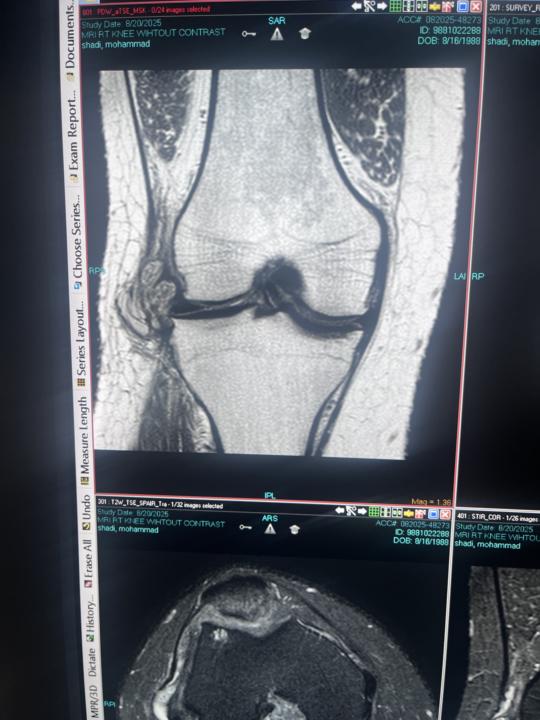

Knee MRI

Hello Please I need your help in this case No post contrast image ,history of knee scope 3yrs ago

Seems to be big parameniscal ganglion. Have some junior general practiotioner put needle in to it before MRI?